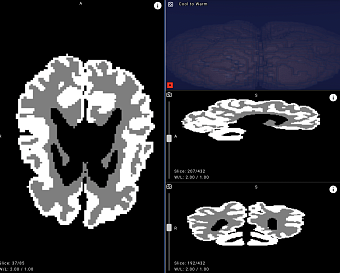

Белорусские врачи смогут точнее выявлять ДЦП у новорожденных с помощью нейросети

Яндекс представил первую в мире нейросеть, которая помогает врачам оценить развитие мозга малышей уже в первые месяцы жизни.